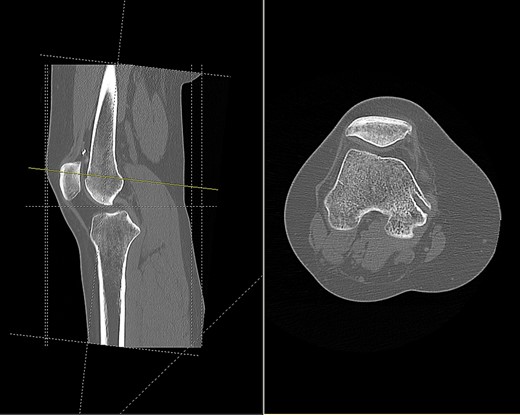

CT (Fig. 1) and MR imaging showed an endobutton and endocord sitting superior to the patella, with both impinging upon the articular surface of the medial patella facet. A metal susceptibility artefact was seen at the medial femoral condyle, which was identified as an interference screw.

CT scan of the right knee showing the endobutton in suprapatellar pouch (sagittal and axial view).